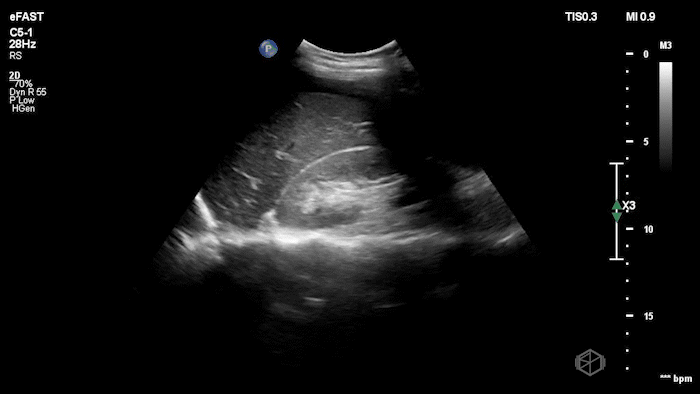

Dr.’s Konner and Maher scanned the patient and saw the following:

Initially it appears as though there is anechoic material above the liver and it does seem to make sharp angles. However, Dr. Konner and Dr. Maher utilized color doppler to evaluate the area and noted that it was simply the inferior vena cava. The patient ultimately had a CT scan that demonstrated no emergent findings.

Diagnosis: Potential false positive FAST - Inferior Vena Cava as a mimic of Free Fluid.

• Vessels can mimic free fluid. The IVC and other vascular structures sit right where we look for RUQ fluid and may appear anechoic in a single still frame. Use color doppler when not sure, free fluid will most commonly be at the caudal liver tip, and rarely just above the spine where the IVC sits.

• Always identify known landmarks (diaphragm, liver edge, kidney, spine) in RUQ views. If you see an anechoic region, ask: Does this structure have sharp, well-defined walls (suggesting a vessel)? Does it run longitudinally/continuously (vessel) or is it pooling between structures (free fluid)?